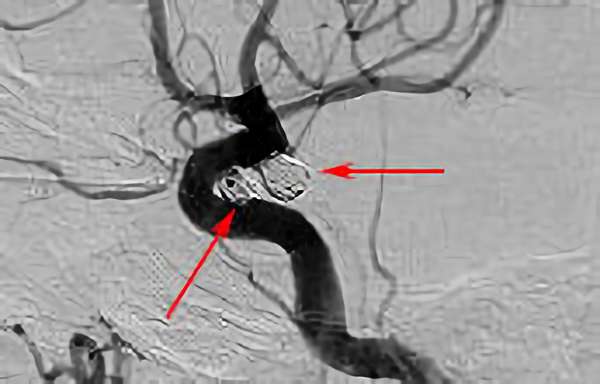

No.1627 手術前

No.1627 手術中

No.1627 手術後